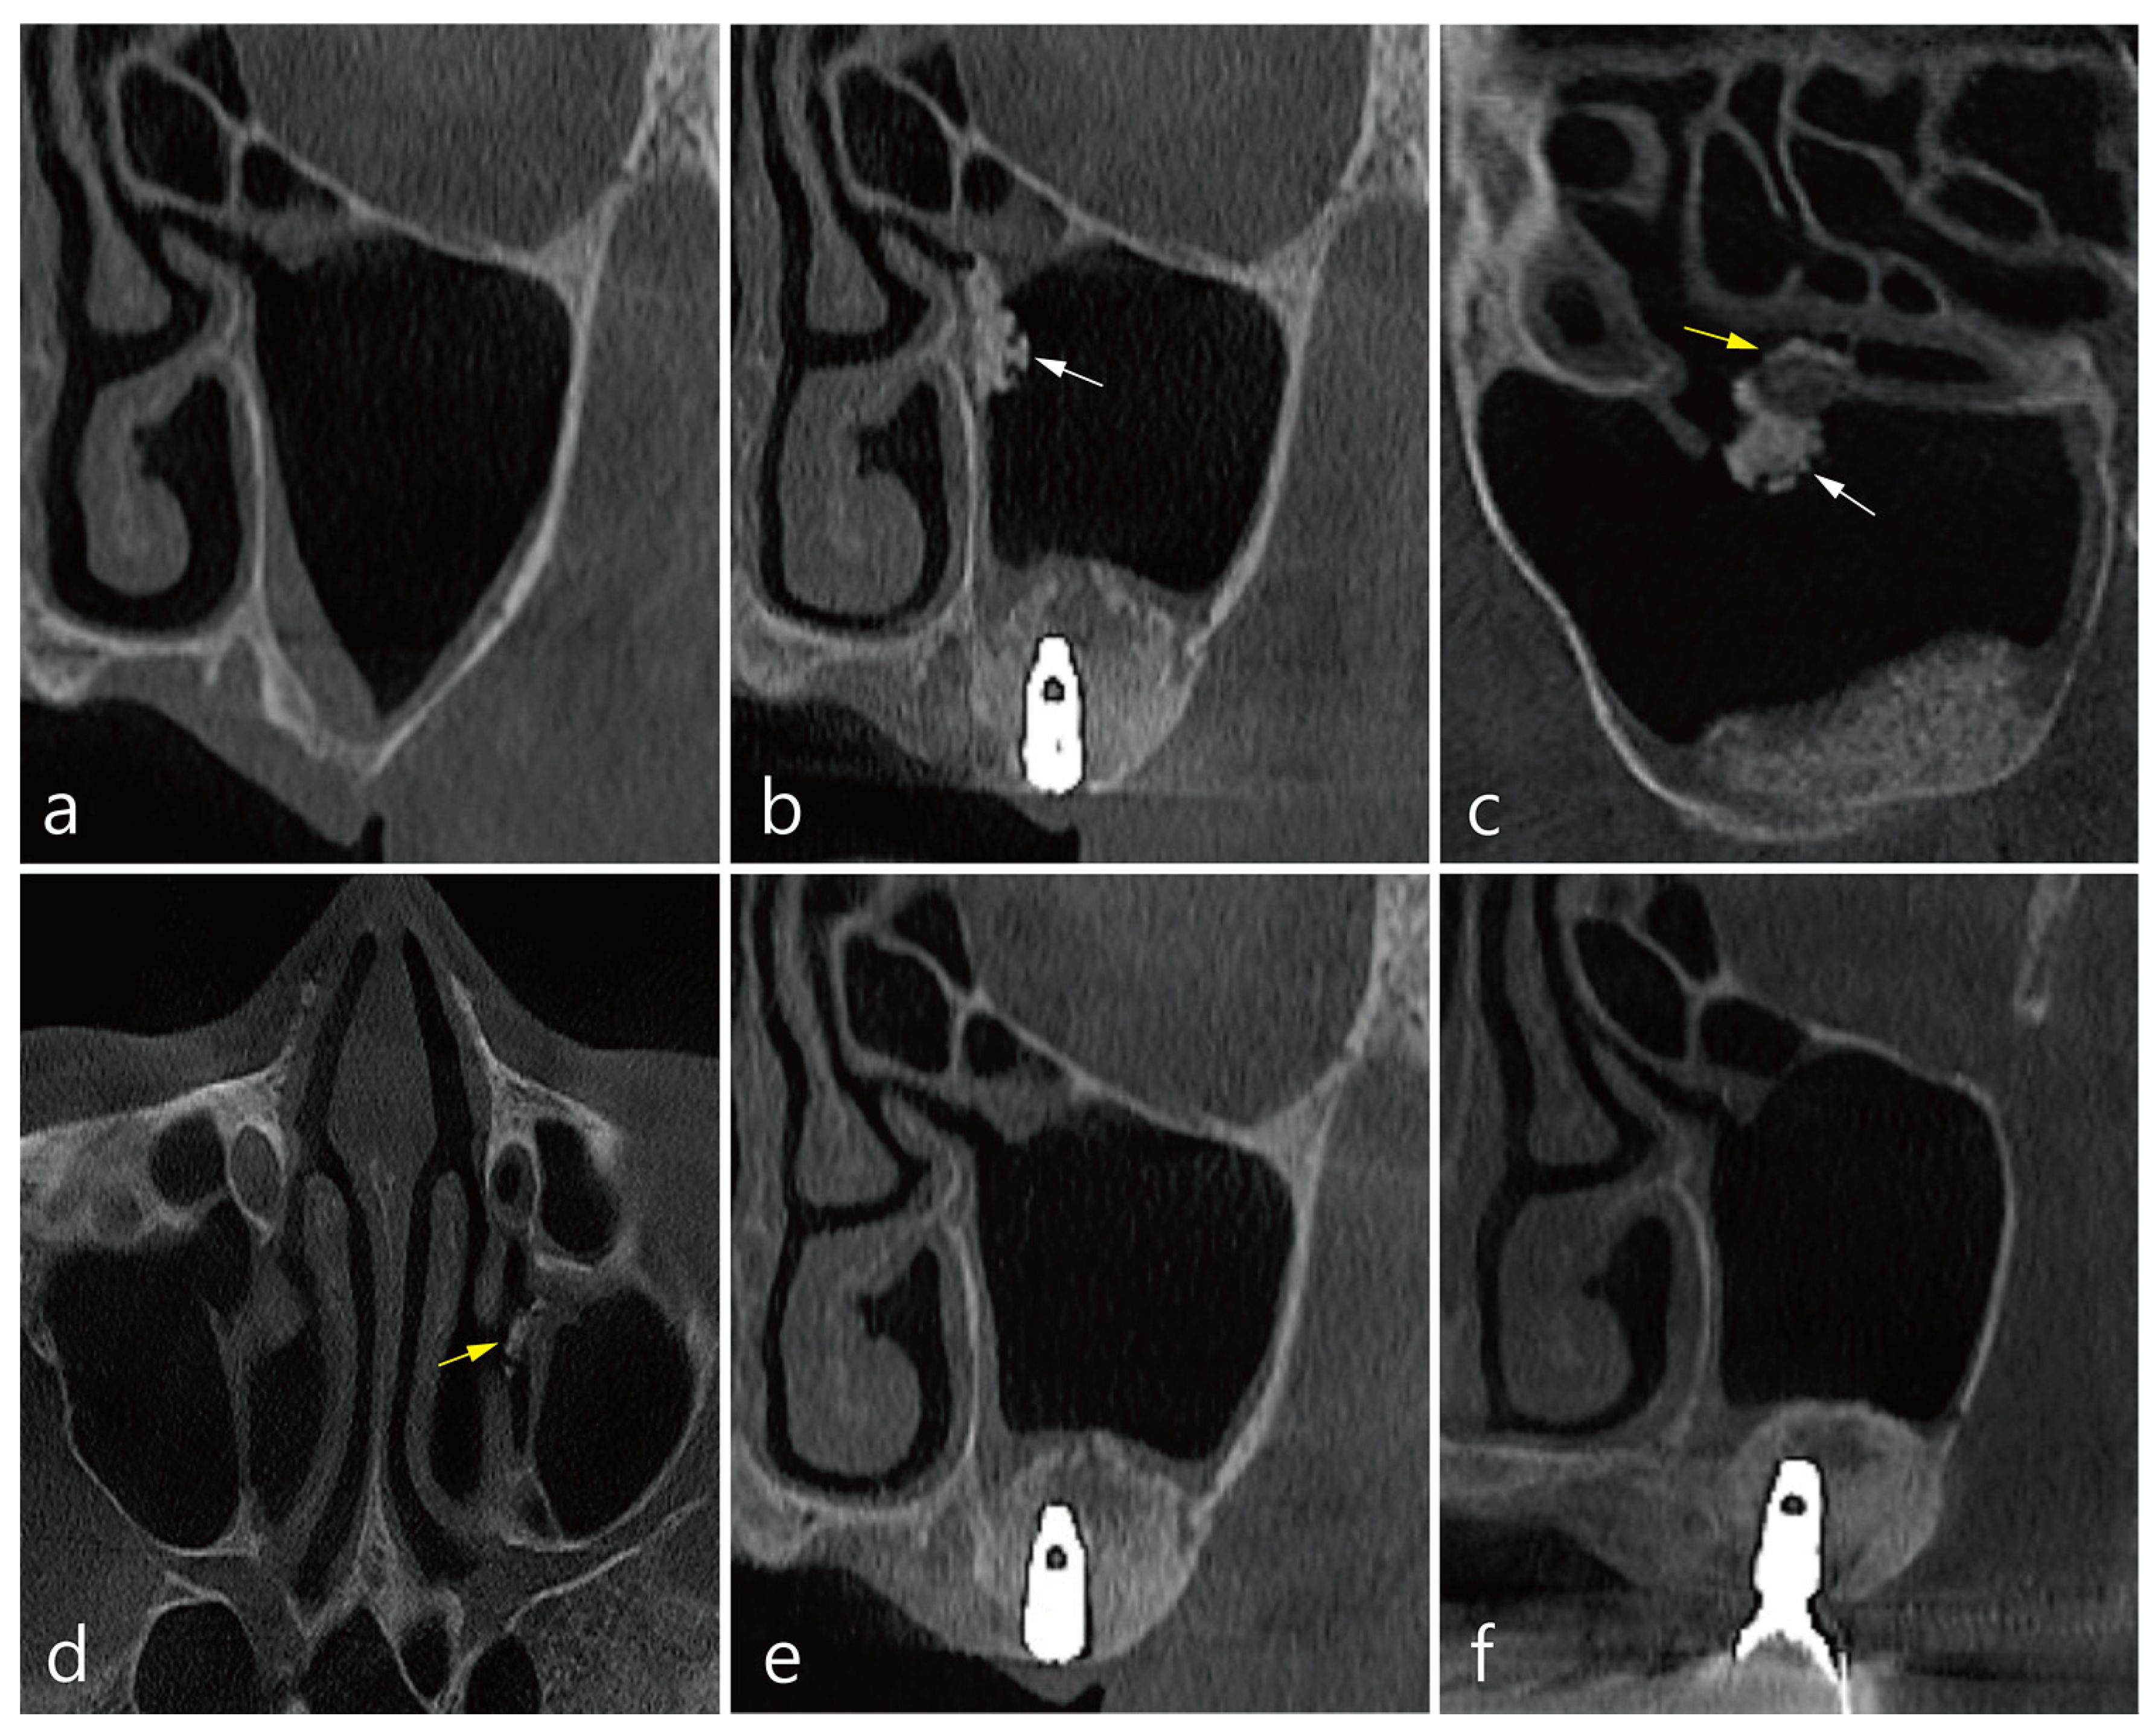

3. Case 1

4. Case 2

5. Case 3

6. Case 4